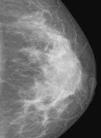

Las calcificaciones mamarias son hallazgos comunes en la mamografía y su frecuencia aumenta con la edad de la paciente. Si bien la mayoría de las microcalcificaciones son originadas en patología benigna, algunos patrones agrupados específicos pueden ser causados por patología maligna o lesiones de alto riesgo1. Es importante diferenciar las microcalcificaciones de origen benigno de las sospechosas puesto que un 55% de los cánceres no palpables se diagnostican mediante la presencia de microcalcificaciones2, y porque las microcalcificaciones son la principal forma de manifestación del carcinoma ductal in situ (CDIS)3. Algunas de estas calcificaciones no solo corresponden a CDIS puro, sino que corresponden a la porción intraductal de carcinomas infiltrantes4.

Las calcificaciones benignas suelen ser más grandes, presentar un aspecto característico y no requerir magnificación. Las sospechosas, en cambio, suelen ser más pequeñas y deben ser estudiadas con placas magnificadas para su caracterización.

La incorporación de sistemas digitales de mamografía tanto directos como indirectos y con utilización de sistemas de detección asistida CAD (del inglés, computer-aided detection)6 ha permitido una mejora en la pesquisa de las microcalcificaciones. El estudio de Vestfold, en el año 2008, encontró una detección significativamente mayor de CDIS mediante mamografía digital7. Cabe destacar, sin embargo, que aún en estos sistemas el requerimiento de placas complementarias magnificadas se mantiene vigente.